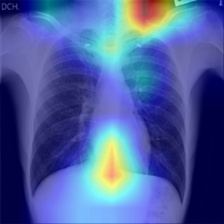

In order to compare the interpretability capacity of our model and the state-of-the-art models, we employ Grad-Cam [18] for heatmap visualizations on selected X-ray images. We show on a side-by-side basis how our model performs with superiority in Figures 4-7. We also observe that the addition of the attention block has a crucial role in focusing on the most relevant features in the images, which significantly assists the model during classification.